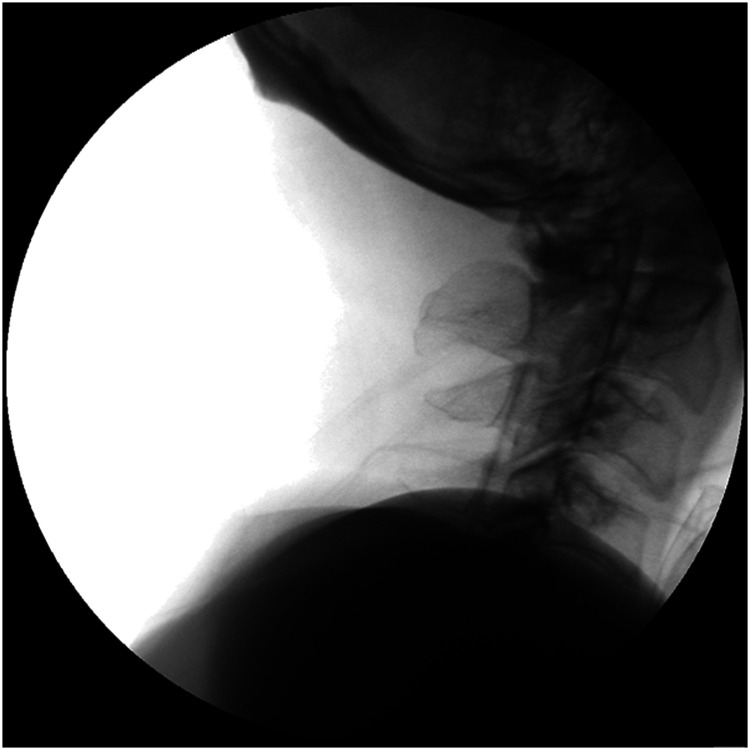

颈神经根病的发病率约为85 / 100000,其特点是颈神经根断裂引起疼痛。由于缺乏普遍接受的黄金标准,准确诊断具有挑战性,需要依赖患者病史、临床检查和诊断测试。臂丛神经转移是一种罕见但临床意义重大的疾病,可以模仿常见的肌肉骨骼疾病,如颈椎神经根病。其非特异性表现往往导致诊断延迟,特别是在癌症患者表现为持续上肢疼痛。本病例报告探讨了锁骨上臂丛转移的误诊,最初被误解为颈椎间盘突出,62岁男性肺癌病史。尽管接受了颈椎导管神经成形术和其他治疗,但患者持续的右臂疼痛促使进一步的调查。胸部计算机断层扫描和正电子发射断层扫描最终显示转移性鳞状细胞癌延伸至臂丛。该病例强调了对有癌症病史的患者进行全面诊断评估和考虑转移性肿瘤的关键需要。这也凸显了臂丛转移的罕见性和临床意义。它强调了综合护理方法的重要性,解决肿瘤和肌肉骨骼问题,以改善患者的预后。

Cervical radiculopathy, with an incidence of approximately 85 per 100,000 individuals annually, is characterized by pain originating from cervical nerve root disruption. Accurate diagnosis is challenging because of the absence of a universally accepted gold standard, necessitating reliance on patient history, clinical examination, and diagnostic tests. Brachial plexus metastasis is a rare but clinically significant condition that can mimic common musculoskeletal disorders, such as cervical radiculopathy. Its nonspecific presentation often results in delayed diagnosis, particularly in patients with cancer presenting with persistent upper-limb pain. This case report explored the underdiagnosis of supraclavicular brachial plexus metastasis, initially misinterpreted as cervical disc herniation in a 62-year-old man with a history of lung cancer. Despite undergoing cervical-Racz catheter neuroplasty and other treatments, the patient's persistent right arm pain prompted further investigations. Chest computed tomography and positron emission tomography computed tomography ultimately revealed metastatic squamous cell carcinoma extending to the brachial plexus. This case underscores the critical need for comprehensive diagnostic evaluations and the consideration of metastatic neoplasms in patients with a history of cancer. It also highlights the rarity and clinical significance of brachial plexus metastasis. It emphasizes the importance of an integrated approach to care, addressing both oncological and musculoskeletal issues to improve patient outcomes.